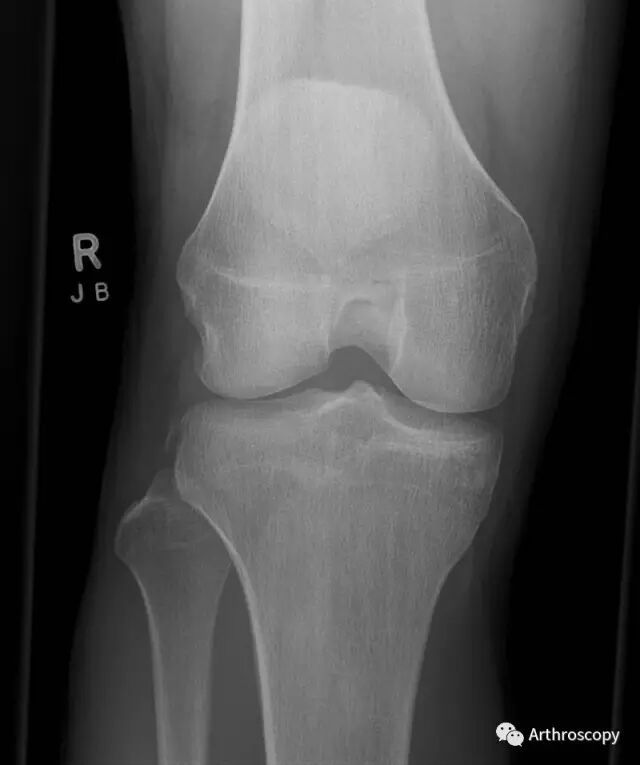

前交叉韧带断裂后手术重建在目前已经得到了广泛的认可,恢复膝关节的稳定是检验膝关节重建术后成功与否的一个重要指标,但是可能你这个没做,你之前做的前交叉韧带重建都白做了。

因为前交叉韧带在限制胫骨前移及膝关节旋转中的作用,因此轴移试验(pivot shift test)在前交叉韧带的体检中有着相应的理论基础。

但是,随着膝关节周围韧带结构的不断解剖完善,人们发现,膝关节外侧的前外侧韧带(Anterolateral Ligament ,ALL)在稳定膝关节旋转中有着重要的作用,它可以增加膝关节的旋转稳定性,防止过度内旋。因此,它的存在可能使得我们一直认为的轴移试验在鉴别前交叉韧带损伤中的特异性大打折扣。

综上,研究发现ALL位于股骨外侧髁外侧副韧带止点的前下方与胫骨Gerdy结节和腓骨头的中间,维持膝关节旋转稳定。

因此,Arth君认为:在Segond骨折的前交叉损伤及术后重建前交叉韧带后有旋转不稳时,应考虑重建前外侧韧带。